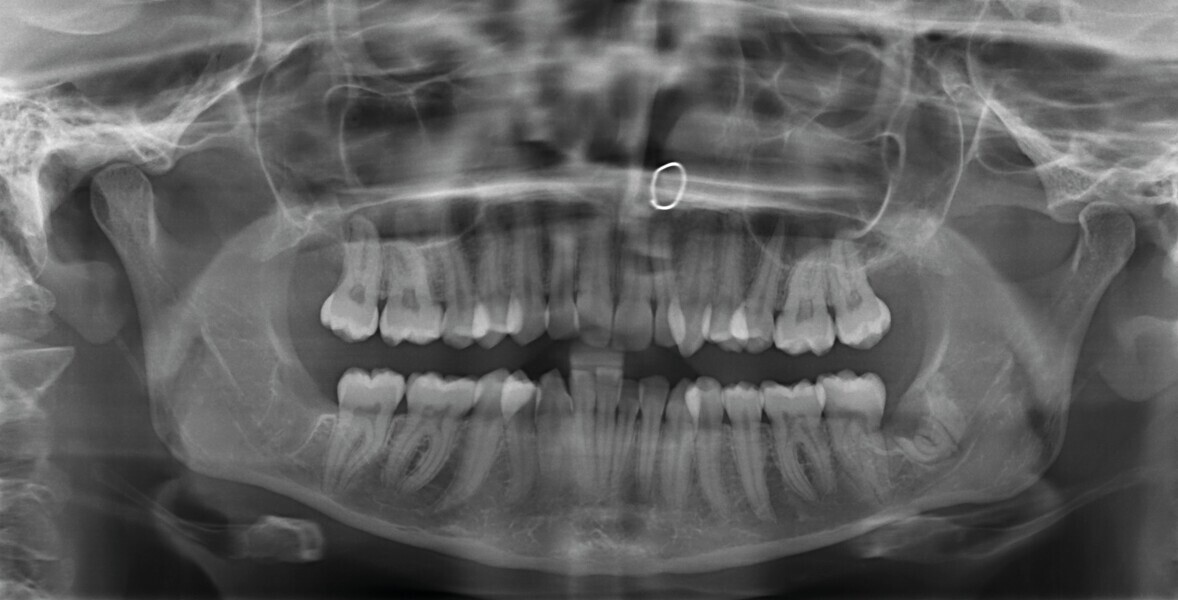

Fig. 2 : Radiographie panoramique initiale.

L’analyse radiographique indique une structure et une morphologie normales des racines. Un vestige radiculaire est encore présent dans la zone de la dent 38 qui a été extraite (Fig. 2). L’analyse céphalométrique montre un schéma squelettique de classe I avec vestibulo-version légèrement marquée des incisives maxillaires et mandibulaires (Fig. 3).